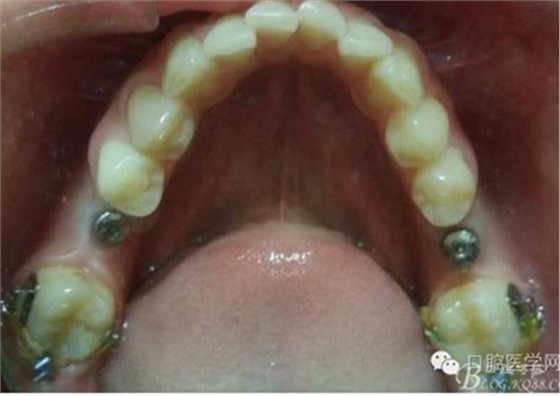

術(shù)前口內(nèi)照片:

模型